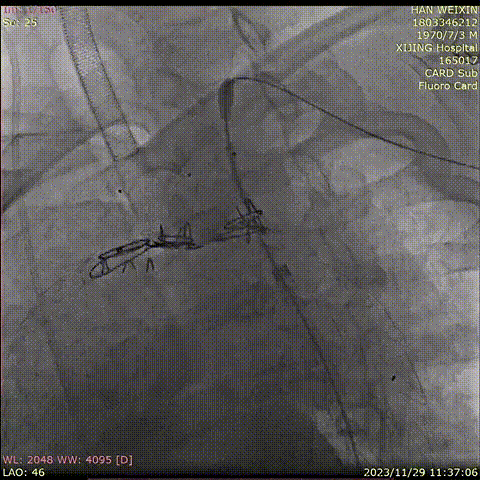

★ 病例5

曹某,男,58岁,“左颈部疼痛伴胸背部疼痛14天”入院,主动脉CTA提示:主动脉弓部夹层,夹层累及左颈总动脉和左锁骨下动脉起始部,弓降主动脉假腔形成,部分已血栓化。

术前CTA

术前造影

术后造影

手术用时 102 分钟